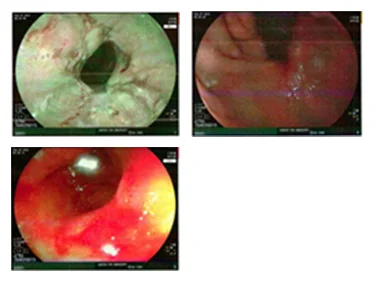

This case involves a 68-year-old male patient with long-segment non-dysplastic Barrett’s esophagus and high anxiety stemming from the loss of his brother to esophageal adenocarcinoma.

- BMI 28 (overweight)

- Chronic GERD for 30 years

- Daily PPI: Rabeprazole 40 mg

- Non-smoker

- Brother has EAC (T3N1Mx)

- Has been in surveillance program for NDBE every 3-5 years